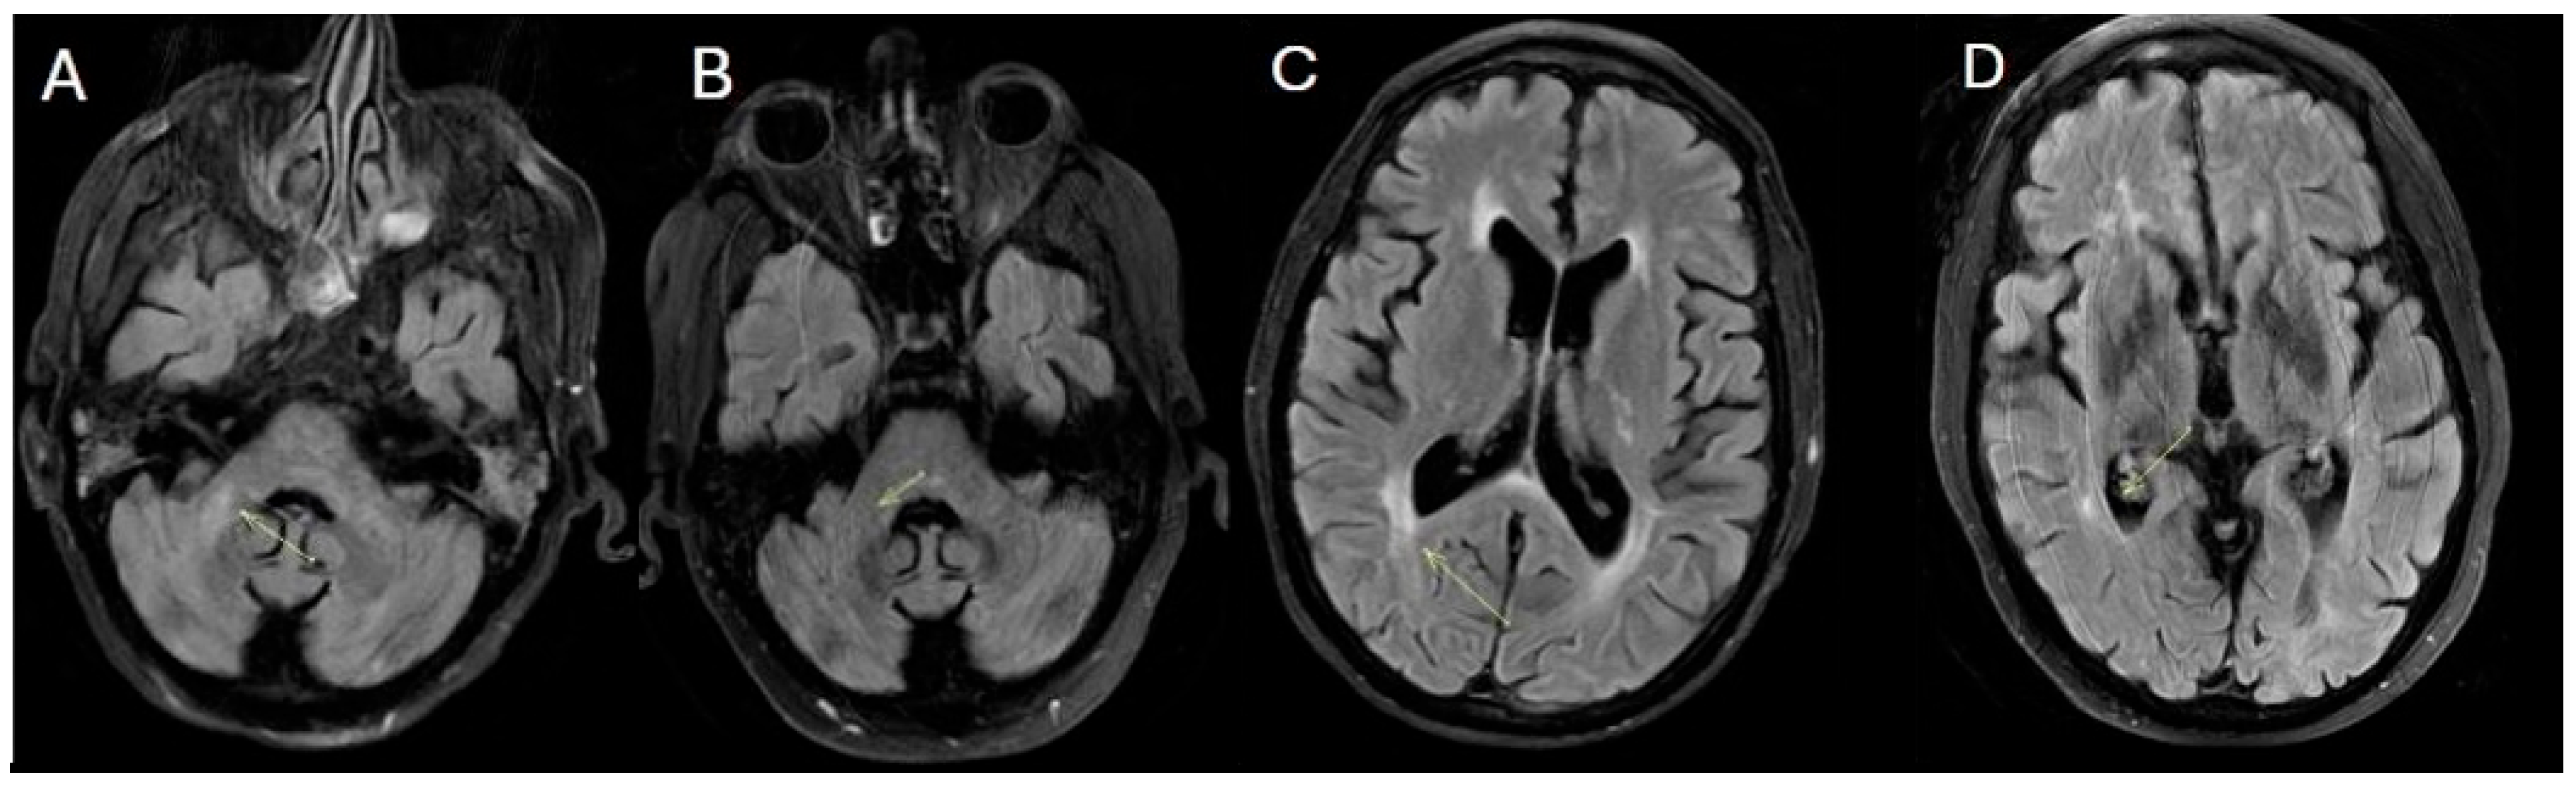

Magnetic Resonance Imaging (MRI) revealed multiple white matter lesions, hyperintense on FLAIR sequences and contrast-enhancing on T1-weighted images, with an asymmetric and periventricular distribution in the brain and spinal cord (Figure 1).

Figure 1. Contrast-enhanced T1-weighted (A,C,F,H), fluid-attenuated inversion recovery (FLAIR) (B,D,E) and STIR (G) images from the patient at baseline (October 2021). The images show multiple hyperintense FLAIR and contrast-enhancing white matter lesions with an asymmetric and periventricular distribution in the brain. Similar lesions are present in the spinal cord.